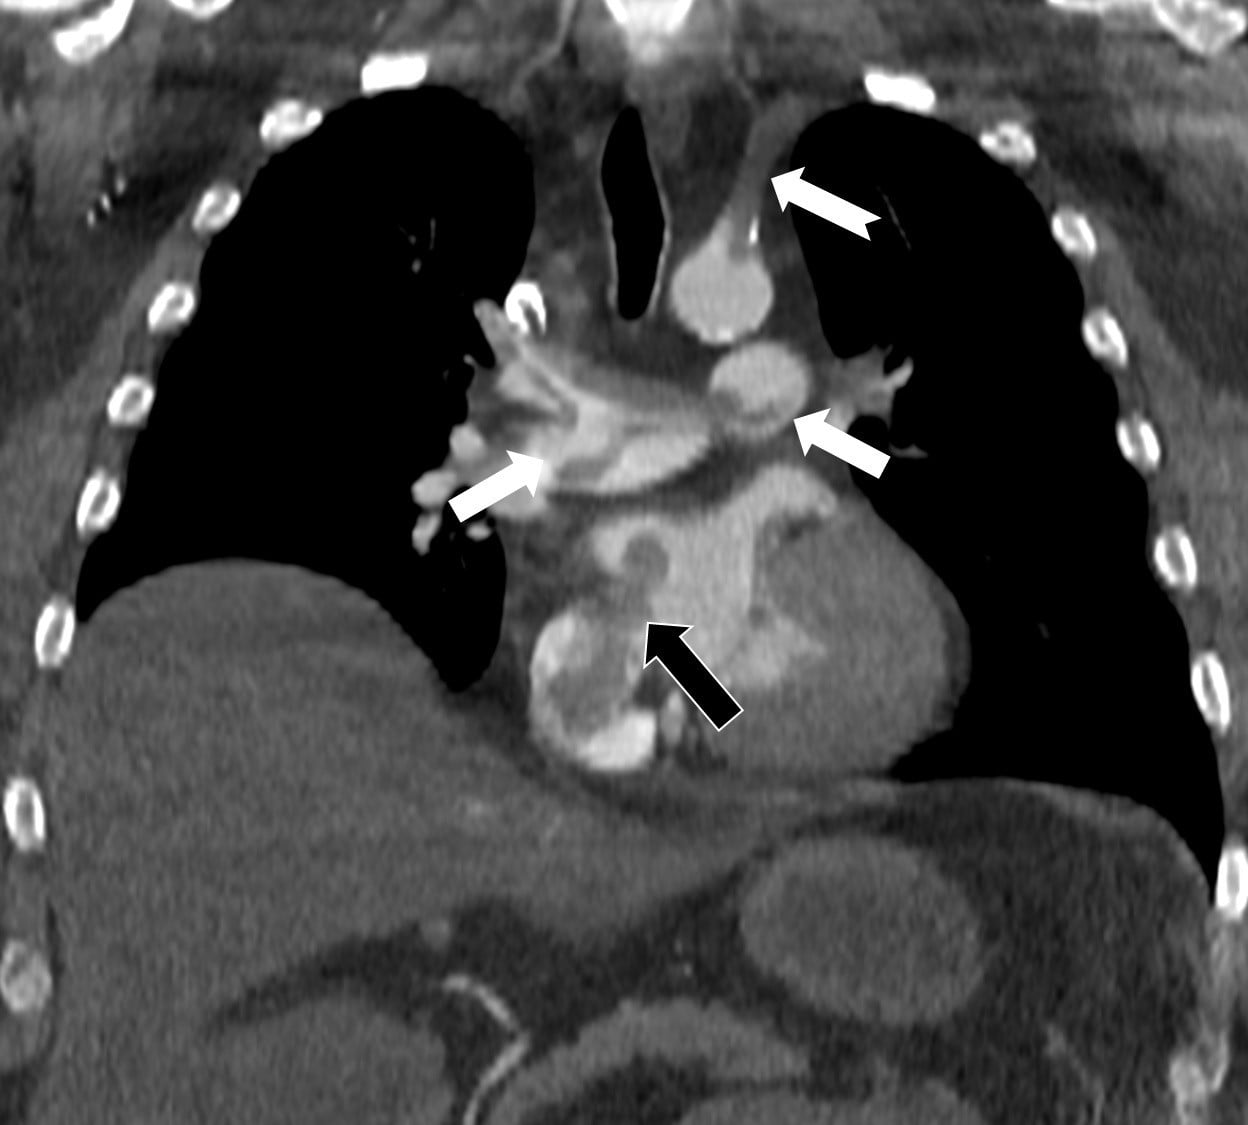

Çalışmada sunulan olguda, 60 yaşındaki bir hasta, penis ameliyatından 5 gün sonra ani göğüs ağrısı, nefes darlığı ve kol uyuşması şikâyetleriyle hastaneye başvurdu. Yapılan bilgisayarlı tomografi anjiyografisi incelemesi, toplar damarlardan kaynaklanan pıhtının akciğer damarlarını tıkadığını gösterdi. Aynı zamanda görüntüleme, pıhtının kalpte daha önce fark edilmemiş bir delikten (atriyal septal defekt) geçerek sağdan sola yönelip ana atardamara ulaşması ve sol kol damarını tıkaması bulgusunu ortaya koydu.

Prof. Dr. Karabulut’un çalışması, bacak damarlarından kaynaklanan pıhtıların yalnızca akciğer embolisine yol açmakla kalmayıp; kalp deliği varlığında ana atardamar yolu aracılığıyla beyin, kol ve bacak gibi bölgelere geçerek ani damar tıkanmasına (paradoks emboli) neden olabileceğini vurguluyor. Çalışmada, nedeni bilinmeyen pıhtı atmalarında kalpteki gizli deliklerin mutlaka araştırılması gerektiği belirtildi.

Makale, ekokardiyografi ve bilgisayarlı tomografi tetkiklerinin erken ve doğru tanı koymada hayat kurtarıcı rol oynadığını işaret ediyor; çalışmada bu görüntüleme yöntemlerinin birlikte kullanılmasının kritik olduğu vurgulanıyor.